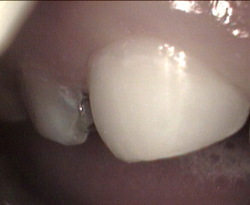

failed sealant has decay restored with white filling

old leaky sealant and decay restored